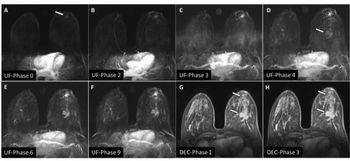

Figure 1. A: Original image. B: Filtered image. C: Normalized image overlaid with left and right individual thalamus regions. Figure 2. Mean and 95% confidence interval of thalamic volumes relative to control subjects (bars) and relative to the patient (points). The volume of the left thalamus was 3.89 cm3 while right thalamus was 3.71 cm3. The values of matched healthy control subjects were 4.58 cm3 ± 0.26 cm3 for the left thalamus and 4.10 cm3 ± 0.23 cm3 for the right thalamus. All volumes were calculated accounting for total intracranial volume.

Because schizophrenic patients with this phenotype may have morphometric changes in the thalamus, MRI was performed to confirm this association prospectively. Three-D high-resolution whole-brain volume imaging was performed using a radiofrequency spoiled gradient-echo T1-weighted sequence on a 1.5T Intera MRI system (Philips Medical Systems). Acquisition parameters were as follows: 96 axial slices covering the whole brain; TR = 7 msec; TE = 1.9 msec; flip angle = 8º; slice thickness = 1.25 mm with no interslice gap; acquisition matrix = 256 x 256; field-of-view = 220 mm (voxel size = 0.86 x 0.86 x 1.25 mm).

Acquired data were processed with SPM2 (Statistical Parametric Mapping, Wellcome Institute), under a MATLAB (MathWorks) platform. First, a nonlocal filter was applied to reduce noise and improve contrast between tissues. The T1 volume was then normalized with a custom template and segmented to obtain gray matter tissue maps. This stage of segmentation involved a cleaning process that removed nonuseful tissue such as scalp, skull, and dural venous sinus. Afterwards, nonlinear spatial normalization parameters between gray matter segmented images and a gray matter template map were estimated and applied in order to warp the original T1 volume. Images were segmented and a region of interest was defined around the left and right thalamus.